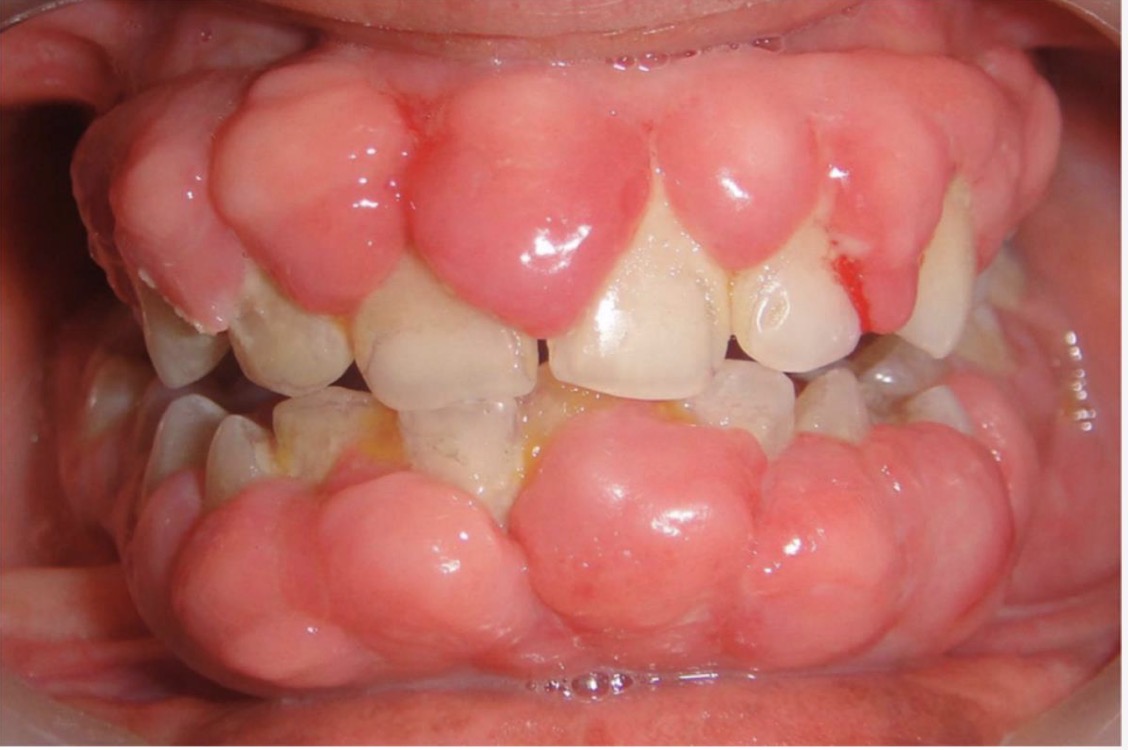

BN CÓ GAI NƯỚU TĂNG SINH, SƯNG TO, CẮNG BÓNG

SỜ DAI, KHÔNG ĐAU, KHÔNG CHẢY MÁU *

CHẨN ĐOÁN

TRIỂN DƯỠNG NƯỚU DO THUỐC PHENYTOIN

TRIỂN DƯỠNG NƯỚU DO DÙNG THUỐC PHENYTOIN

CHẨN ĐOÁN?